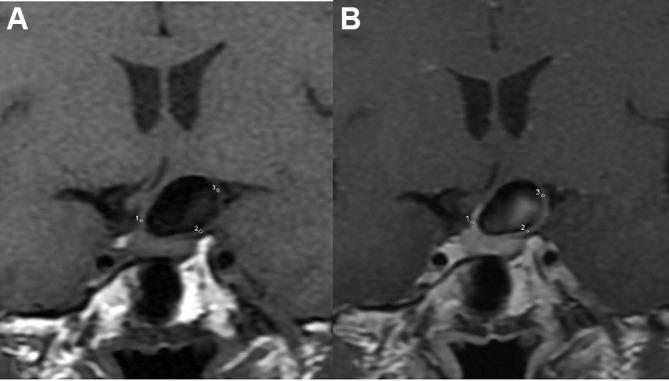

91 consecutive patients with 106 IAs were reviewed from February 2016 to April 2017. Patients and IAs were divided into ruptured and unruptured groups. In addition to the clinical characteristics of the patients, the features of IAs (eg, shape) were evaluated by CT angiography, whereas wall thickness, enhanced patterns, and enhancement ratio (ER) were evaluated by MRI. Multiple logistic regression analysis was used to identify independent risk factors associated with the rupture of IAs. Receiver operating characteristic curve analysis was performed on the final model, and the optimal thresholds were obtained.

ER (OR 6.638) and partial wall enhancement (PWE) (OR 6.710) were not markers of aneurysms more prone to rupture, but simply were more commonly found in the ruptured aneurysm cohort. The threshold value for ER was 61.5%.

ER (≥61.5%) and IAs with PWE are better predictors of rupture. Increased attentions should be paid to these factors during assessment of IA rupture.